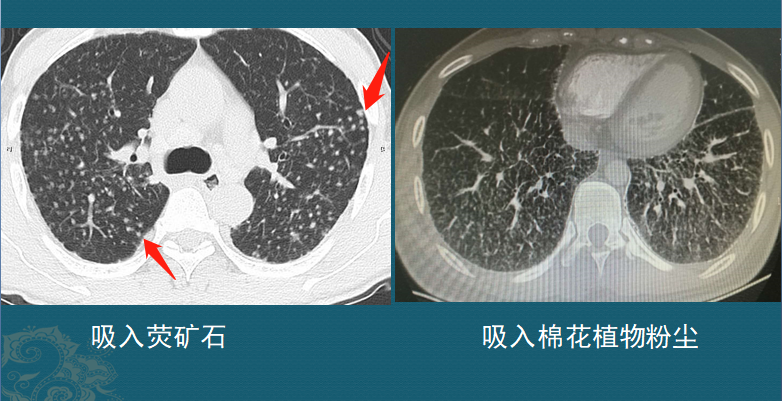

肺结节是怎么长出来的?医生用ct片详解,有2种可能是肺癌